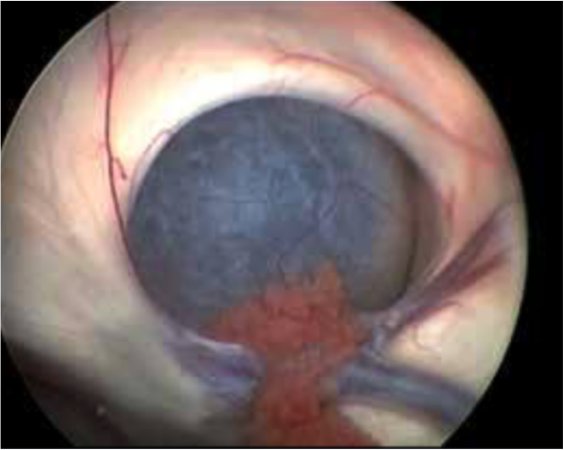

Bei dem Endoskop handelt es sich um ein optisches Lichtleitungssystem, an das eine Kamera angeschlossen ist. Darüber hinaus ist es mit einem Spül- und Arbeitskanal zum Einbringen von Miniaturinstrumenten wie Fasszangen, Ultraschallsonden oder Ballonkathetern ausgestattet.  Der Operationszugang ist über einen bleistiftdünnen Kanal möglich. Die Kamera ermöglicht es, gestochen scharfe Bilder in Full-HD-Qualität aus verschiedenen Perspektiven auf einen hoch auflösenden Bildschirm zu übertragen. Verschiedene Winkeloptiken ermöglichen die umfassende Inspektion aller Bereiche. Das verschafft dem Operateur einen detailreichen Blick auf das Operationsfeld mit seinen empfindlichen Strukturen wie Blutgefäßen oder Nerven, wodurch die Operationssicherheit gesteigert wird.

Uns stehen drei Endoskopie-Systeme zur Verfügung. Eines dient der transventrikulären Endoskopie. Dieses Instrument wird durch den Ventrikel (Nervenwasserkammer) eingeführt und zur Entfernung von Tumoren, zur Herstellung von Verbindungen innerhalb der Nervenwasserkammer und zu den Räumen außerhalb des Gehirnes, aber auch zur Probeentnahme von Tumoren, die neben der Mittellinie liegen, genutzt.

Tumoren und Zysten in den Hirnkammern können über ein kleines Bohrloch im Schädel so oft sicher und schonend entfernt werden. In Kombination mit modernster Neuronavigation und intraoperativer Bildgebung kann sich der Chirurg genau im OP-Gebiet orientieren und das Endoskop exakt positionieren. Das sind optimale Voraussetzungen für die Behandlung hochkomplexer Erkrankungen.